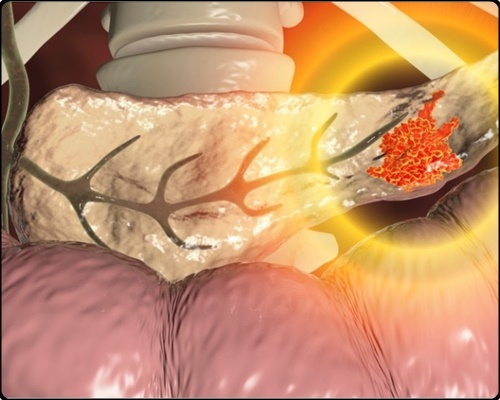

췌장은 소화효소와 인슐린, 글루카곤 등의 호르몬을 분비 및 담당하는 역할을 주로 담당합니다. 그런데 췌장에 종양이 발생하면 췌장암이라고 해요. 췌장암의 경우 사망 확률이 높은 암이라서 조기발견이 무척 중요하더라고요. 다른 질병과 증상이 비슷하며 발견될 때에는 이미 전이가 상당히 진행되는 만큼 조기발견이 힘든 암이기도 해요. 췌장암 초기증상 및 췌장암 등통증 부위에 대해 알아볼게요.

환자의 약 90%가 암 진행이 많이 진행된 상태로 암이라는 것을 발견하게 되고 때문에 치료가 쉽지 않은 암 중 하나입니다. 이러한 췌장암의 초기 증상을 살펴보도록 하겠습니다.